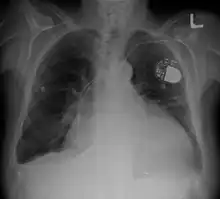

Radiographie thoracique montrant une cardiomégalie avec un pacemaker visible en haut à droite de la photo, la silhouette cardiaque occupant plus de la moitié du diamètre transversal du thorax

La cardiomégalie est une augmentation anormale de la taille du cœur[1]. Elle peut être dépistée par une radiographie thoracique de face, en position debout, montrant un index cardiothoracique supérieur à 0,5 ou 0,55. Cet index est égal au rapport entre le plus grand diamètre horizontal du cœur et le plus grand diamètre horizontal du thorax, mesurés sur une radiographie thoracique conventionnelle.